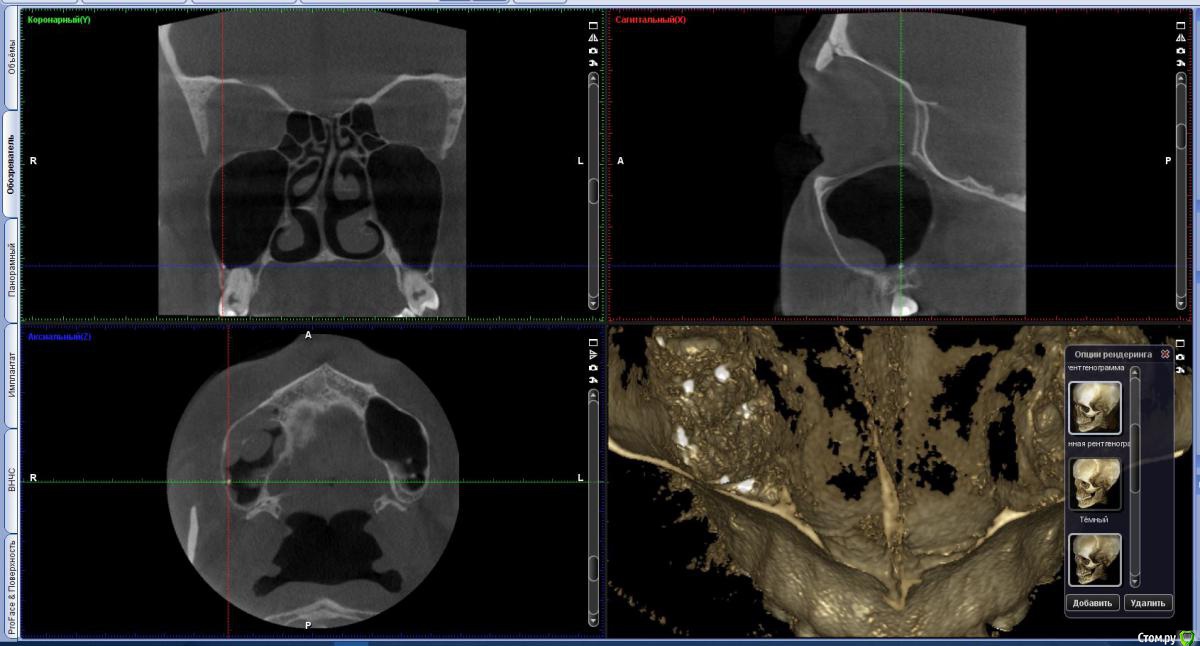

vicTORYa Опубликовано 24 мая, 2016 Поделиться Опубликовано 24 мая, 2016 Здравствуйте.В сентябре 2015 года лечила зубы с правой стороны.Снимок до леченияЛечили нижние 4,5,6,7,8 и верхние 3,4,5,6,7,8 зубы справа. В 5 и 7 верхних зубах случилась перфорация пазухи, врач поставил ультракал на месяц. Остальные зубы запломбировал постоянными пломбами, в каналы гуттаперчю поставил.В октябре пришла долечить 5 и 7 зубы. 5 запломбировали, а в 7 обнаружилась перфорация корня, врач запломбировал этот перфорированный канал какой-то специальной пастой (названия не помню). Два верхних и три нижних подготовил под коронки. Коронки решили ставить позже.Всё ждала, когда боль пройдет, но в некоторых зубах она так и не прошла, на тот момент при нажатии на зубы или постукивание болели 5, 6, 7 верхние (кажется 8 тоже), нижний 7 и немного ныл 5 нижний. Сделала панорамный снимок и пошла к врачу, он направил к ЛОРу так как увидел пятно в пазухе.Снимок на тот моментЛОР послал на КТ пазух.Сказал, что это кистозно-полипозное образование и его нужно удалять.Так ничего и не делала, оставила ситуацию в подвешенном состояние так как я в полной растерянности.На данный момент болят при постукивание верхние 5,6,7, 8 но совсем немного, при нажатие 6,7. Нижний 7 болит при нажатий и постукивание, немного 5 (и как будто ноющая боль бывает).Свежий снимок.Помогите пожалуйста разобраться. Что с этими зубами? Почему они продолжают болеть? Насколько большая проблема материал, выступивший за предел корня? Нет ли вокруг него воспалительного процесса? И что мне с ними делать дальше? Одевать ли коронки? Или может какие-то из них вообще подлежат удалению? Что с пазухой? Если нужны какие-то другие срезы из КТ могу выложить. Заранее спасибо. Ссылка на комментарий

Паращук Роман Опубликовано 24 мая, 2016 Поделиться Опубликовано 24 мая, 2016 В верхних зубах материал за пределами корня и скорее всего в пазухе. Может стать причиной воспалительных процессов или усугубить их,или поддерживать. В нижней 7ке выведенная гуттаперча за пределы канала. Если есть проблемы,то их нужно решать или организм решит их за вас. В верхних зубах эндоскопически через носовой ход,в нижнем попробовать через каналы,если нет хирургически. Ссылка на комментарий

vicTORYa Опубликовано 13 июня, 2016 Автор Поделиться Опубликовано 13 июня, 2016 Спасибо за ответ. Прояснили мне ситуацию. Немного начинаю понимать, что делать.То, что проблемы нужно решать я понимаю, не понимала как. Стоматолог (на то что они болят уже на протяжение более полугода и значит там что-то не так) посмотрел снимок, постучал по зубам сказал, что все в порядке с зубами, нужно ставить коронки, а вот пятно в пазухе не хорошо и надо сходить к лору. Лор сказал, что надо удалять эту кисту, которая там образовалась. Но ничего не сказал про пломбировочный материал. Поэтому я ничего так и не сделала до сих пор со всем этим, так как не совсем понимала зачем удалять кисту если не решать проблемы с зубами, ведь она там может опять появится, и вот оказывается еще и другие проблемы давать. И как ставить коронки если зубы болят.С другой стороны, боль в зубах постепенно снижается, зимой болели сильней, на данный момент немного болит 6,7 верхние и 7 нижний при постукивании или нажатие. И еще немного 5 нижний, но там другая боль какая-то, немного болит десна при надавливании на неё, а сам зуб болит как будто на нем долго жевали, в общем даже не знаю, как описать)Если подытожить, правильно ли я поняла? Зубы эти удалять не нужно, а нужно решать проблемы с материалом пломбировочным, и потом можно ставить коронки? И ещё вопрос, можно ли подождать ещё пару месяцев и если боль совсем пройдёт, то ставить коронки и нижние не перелечивать, а верхние удалять эндоскопически через нос? Ссылка на комментарий